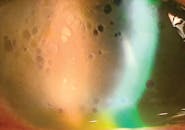

Cornea/Anterior Segment